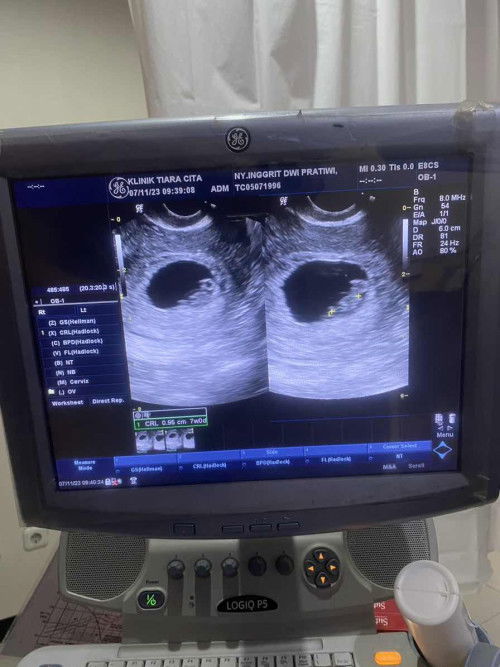

USG 8 week

Halo bunda” sharing yuk. Kebetulan hpht saya 31okt. Waktu itu Saya coba testpack dan trnyata hasilnya garis dua. Saya lgsung priksa ke dr kandungan dan usg pda saat usia kandungan 5week. Tp kata dokter nya blm trlihat ap2. Dokter suruh kmbali lgi 3mnggu kmudian. Kebetulan kmrn saya bru saja kontrol dan usg tpat di usia 8 week. Dan hasil usg nya sprti ini. Mnurut bunda2 smua apakah ini normal dan wajar jika hanya trlihat sprti ini? Krna ada tman yg blg kalu ini hanya penebalan rahim bisa saja janin tdk berkembang dan itu penebalan mau mens. Sedih denger nya. Mohon info dan masukan2 nya ya bunda smuaa 🙏🏻